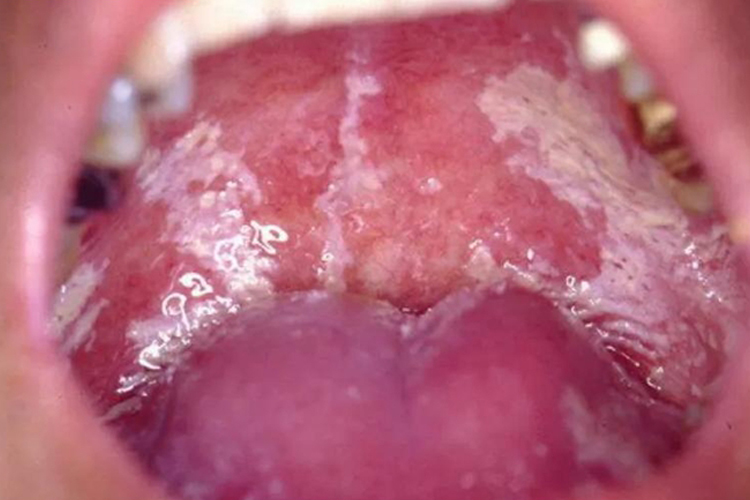

急性假膜型念珠菌性口炎多见于长期使用激素者、艾滋病患者、免疫缺陷者、婴幼儿及衰弱者,又称新生儿鹅口疮或雪口病。好发部位为颊、舌、软腭及唇,损害区黏膜充血,随即出现许多散在的色白如雪的小斑点,略高起,状似凝乳,逐渐增大,不久即相互融合为白色丝绒状斑片,严重者蔓延至扁桃体、咽部、牙龈。早期黏膜充血较明显,斑片附着不紧密,稍用力可擦掉,露出红的黏膜糜烂面及轻度出血。

急性红斑型念珠菌性口炎又称抗生素口炎、抗生素舌炎,多见于长期应用抗生素、激素后及艾滋病患者,并且大多数患者患有消耗性疾病,如白血病、营养不良、内分泌紊乱、肿瘤化疗后等。主要表现为黏膜充血、糜烂,舌背乳头呈团块萎缩周围舌苔增厚,自觉症状为味觉异常或味觉丧失,口腔干燥,黏膜灼痛。